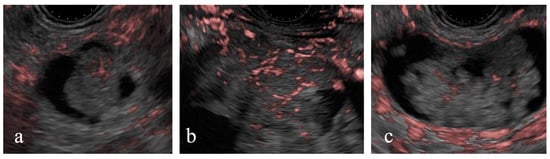

Figure 4. Detective flow imaging (DFI) and contrast-enhanced (CE) endoscopic ultrasonography (EUS) images of mural nodules smaller than 10 mm. Case 1 is observed using DFI-EUS (yellow arrow; a1) and CE-EUS (a2). Case 2 is observed using DFI-EUS (yellow arrow; b1) and CE-EUS (b2). Case 3 is observed using DFI-EUS (yellow arrow; c1) and CE-EUS (c2). DFI-EUS images of linear or dotted vessels inside the mural nodules. All CE-EUS images show homogeneous enhancement.